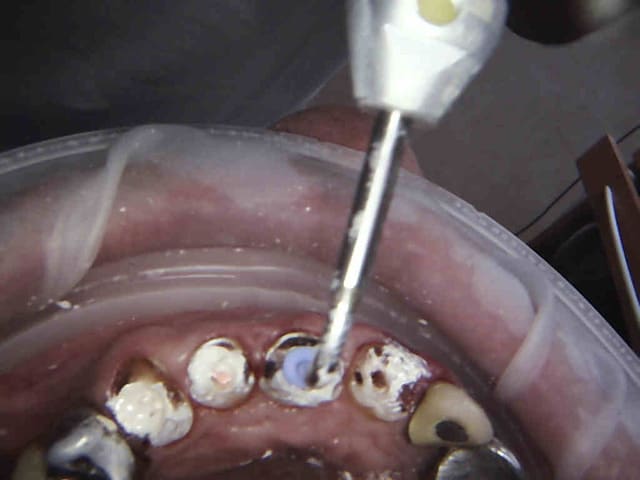

Endo taille empreinte provisoires 2H 30.

Gutta scellée au tubuli seal avec ou sans condensation thermo mécanique.

Logement du tenon réalisé au friendo ( voir photos) qui fond la gutta ( 200 ° au niveau de l'insert) . Un coup de machtou et hop tu peux passer les forets.

Avantage tu peux faire les provisoires et l'empreinte dans la séance et surtout tu peux raser les couronnes ce qui est un réel plus pour les endos surtout avec des pulpes rétractées comme ici ca évite de faire des conneries avec un abord palatin ou on ne voit rien du tout.